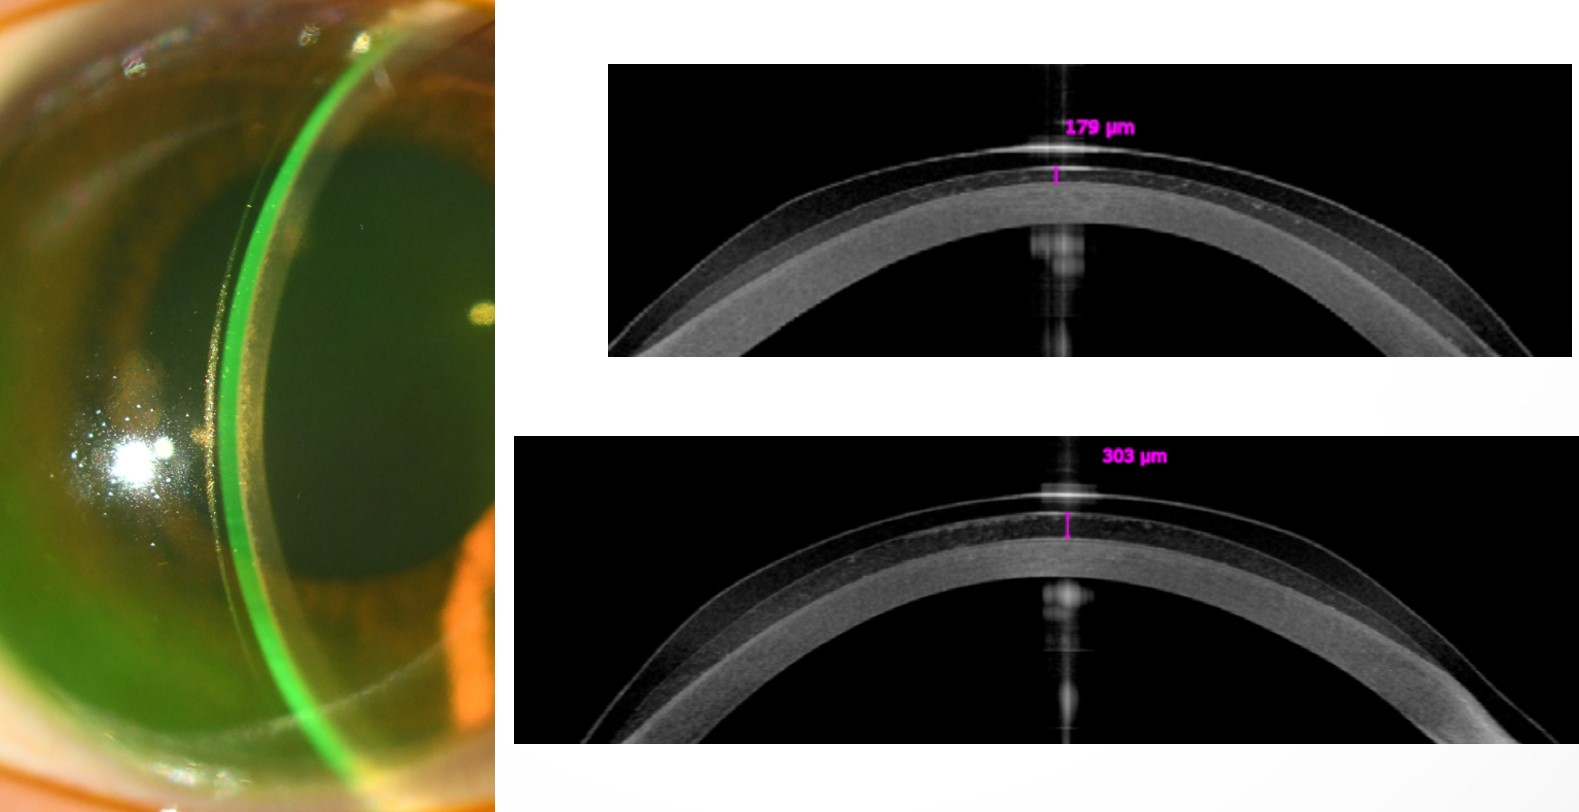

UV-A는 각막내피에 독성을 일으킬수 있어 각막기질 두꼐가 400um이상으로 충분히 두꺼운 경우에 시행합니다.

각막기질 고리 삽입술 (Intacs ring) 삽입술은

INTACS (Intracorneal Ring Segments) 이라하는 단단한 PMMA로 된 아크형태 segment 를 각막기질에 삽입하는 시술입니다.

중심부를 피해서 원추 피크 주변부에 고리 삽입을 통해 원추부분을 편평하게하면서 진행을 늦춥니다.